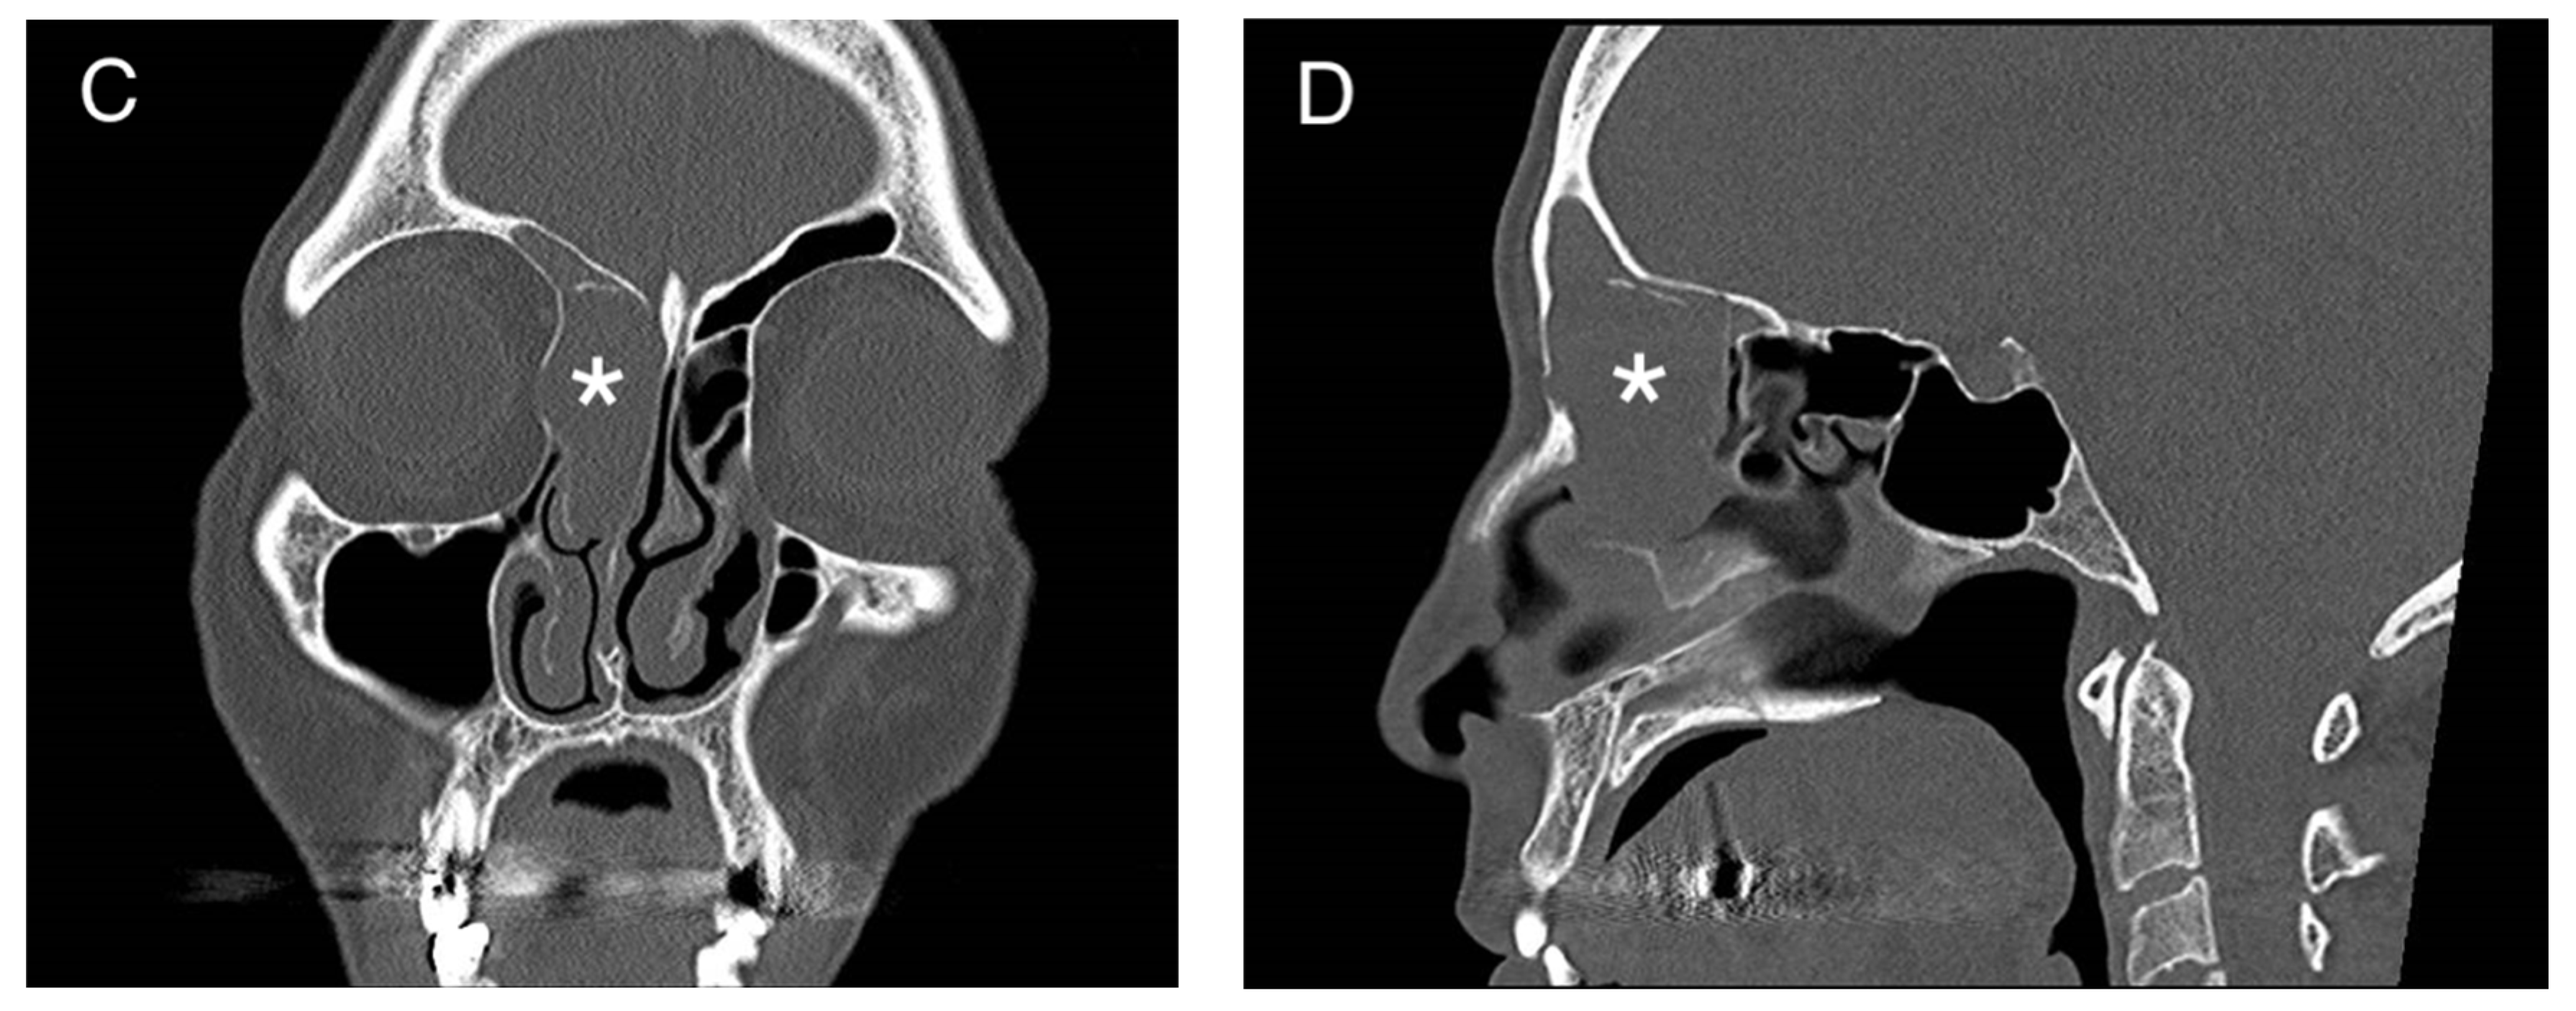

Figure 1.

(A) Preoperative MRI (Time Of Flight TOF sequence in axial view; black asterisk) and CT-scan (B) (axial view; white asterisk) (C) (coronal view; white asterisk), (D) (sagittal view; white asterisk) showing an anterior ethmoidal high vascularized tumor invading the right nasal bone and the medial wall of the right orbit. R = right, P = posterior.